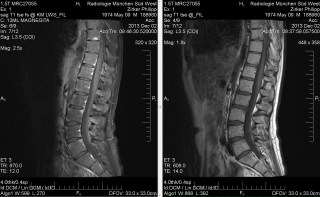

Nötig wurde die ganze Sache, da auf den letzten Röntgenbildern nicht deutlich wurde, wie stark mein Bechterew meine Knochen nun eigentlich in Mitleidenschaft gezogen hat. Außerdem war es wichtig zu erfahren, wo eigentlich die ganzen Entzündungen verortet sind, die die drastischen Blutwerte ergeben haben.

Ich nehme mal das Ergebnis vorweg und zitiere den Befund des Radiologen:

„Es zeigen sich Knochenmarko?deme bzw. eine versta?rkte Kontrastmittelaufnahme im Sinne einer entzu?ndlichen Aktivita?t an praktisch allen Vorder- und Hinterkanten der Wirbelko?rper im Untersuchungsbereich. Daru?berhinaus findet sich eine sog. Andersson-La?sion an der Bodenplatte von BWK 9. Eine versta?rkte Kontrastmittelaufnahme ist auch im Bereich der Kostovertebral- und Kostotransversalgelenke der Wirbelko?rper BWK 10-12 nachweisbar. Degenerative postentzu?ndliche Vera?nderungen sind vor allem in den Facettengelenken LWK 3-5 nachweisbar. Die mitabgebildeten Ileosakralgelenke sind in den kaudalen Anteilen beidseits kno?chern vo?llig durchbaut als Hinweis auf abgelaufene entzu?ndliche Vera?nderungen.“

Oder, prägnant verständlich zusammengefasst:

Typischer Befund eines M. Bechterew mit entzu?ndlicher Aktivita?t an multiplen Wirbelko?rpern sowie im Bereich der Abga?nge der kaudalen Rippen. Postentzu?ndliche Vera?nderungen der Iliosakralgelenke.“

Irgendwie Amüsant: Die erste Frage, die mir der Radiologe gestellt hat war „Bechterew ist bekannt“? Mal angenommen, das wäre mir nicht bekannt gewesen, dann wäre das nun auch nicht unbedingt die schonende Variante gewesen, mir das zu eröffnen. Aber gut, die Aussage kam ja jetzt nicht so überraschend – schon eher mit welcher Eindeutigkeit er das feststellen konnte. Wenn ich mir überlege, wie schwer seinerzeit die ursprüngliche Diagnose zu bekommen war. Aber das ist ja auch schon fast 15 Jahre her.Letztlich haben wir jetzt also den Beweis in Bildern, dass Ibuprofen -in welchen Dosierungen auch immer- nunmal nicht hilft. Womit der Wer zu einer Behandlung mit Enbrel dann wohl geebnet wäre beziehungsweise die Behandlung eben problemlos verargumentiert werden kann. Ich bin gespannt, was meine Rheumatologin morgen dazu sagt.